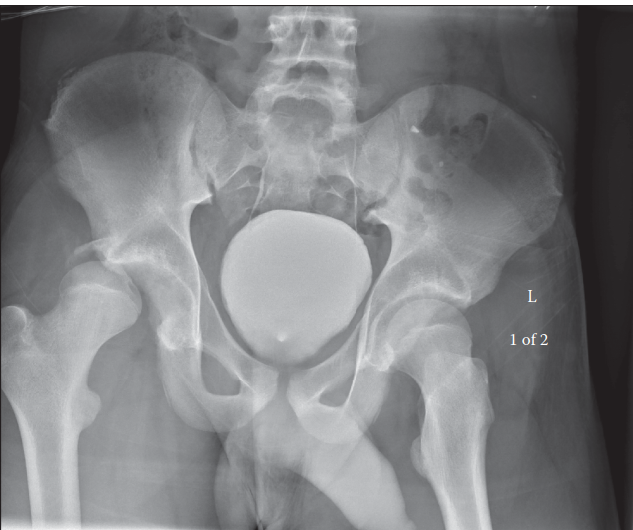

-

الأشعة السينية (X-rays):

- الأشعة الأمامية الخلفية (AP view): تُظهر بوضوح خروج رأس عظم الفخذ من الحُق، وموقعه الخلفي.

- الأشعة الجانبية (Lateral view): تساعد في تأكيد الاتجاه الخلفي للخلع وتحديد وجود أي كسور مصاحبة.

- أشعة الحوض المائلة (Oblique views/Judet views): تُستخدم لتقييم الحُق بدقة والكشف عن الكسور التي قد لا تظهر في الأشعة العادية.

- يستخدم الدكتور هطيف الأشعة السينية فوراً لتأكيد الخلع واستبعاد أي كسور عنقية قد تعيق الرد المغلق.

ج. تأكيد الرد والتقييم بعد الرد:

بعد الرد الناجح، يجب التأكد من استقرار المفصل وعدم وجود أي مضاعفات:

- الأشعة السينية الفورية: تؤخذ أشعة سينية بعد الرد مباشرة للتأكد من عودة رأس الفخذ إلى مكانه الصحيح واستبعاد أي كسور غير مكتشفة أو شظايا عظمية داخل المفصل.